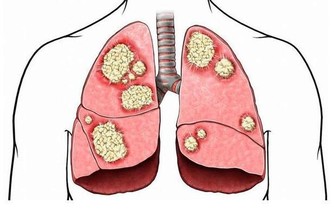

(8)腹部脹氣

當肝臟受損,肝功能異常,肝臟合成的膽汁數量就會下降,具體表現就是消化不良、腹部脹氣。